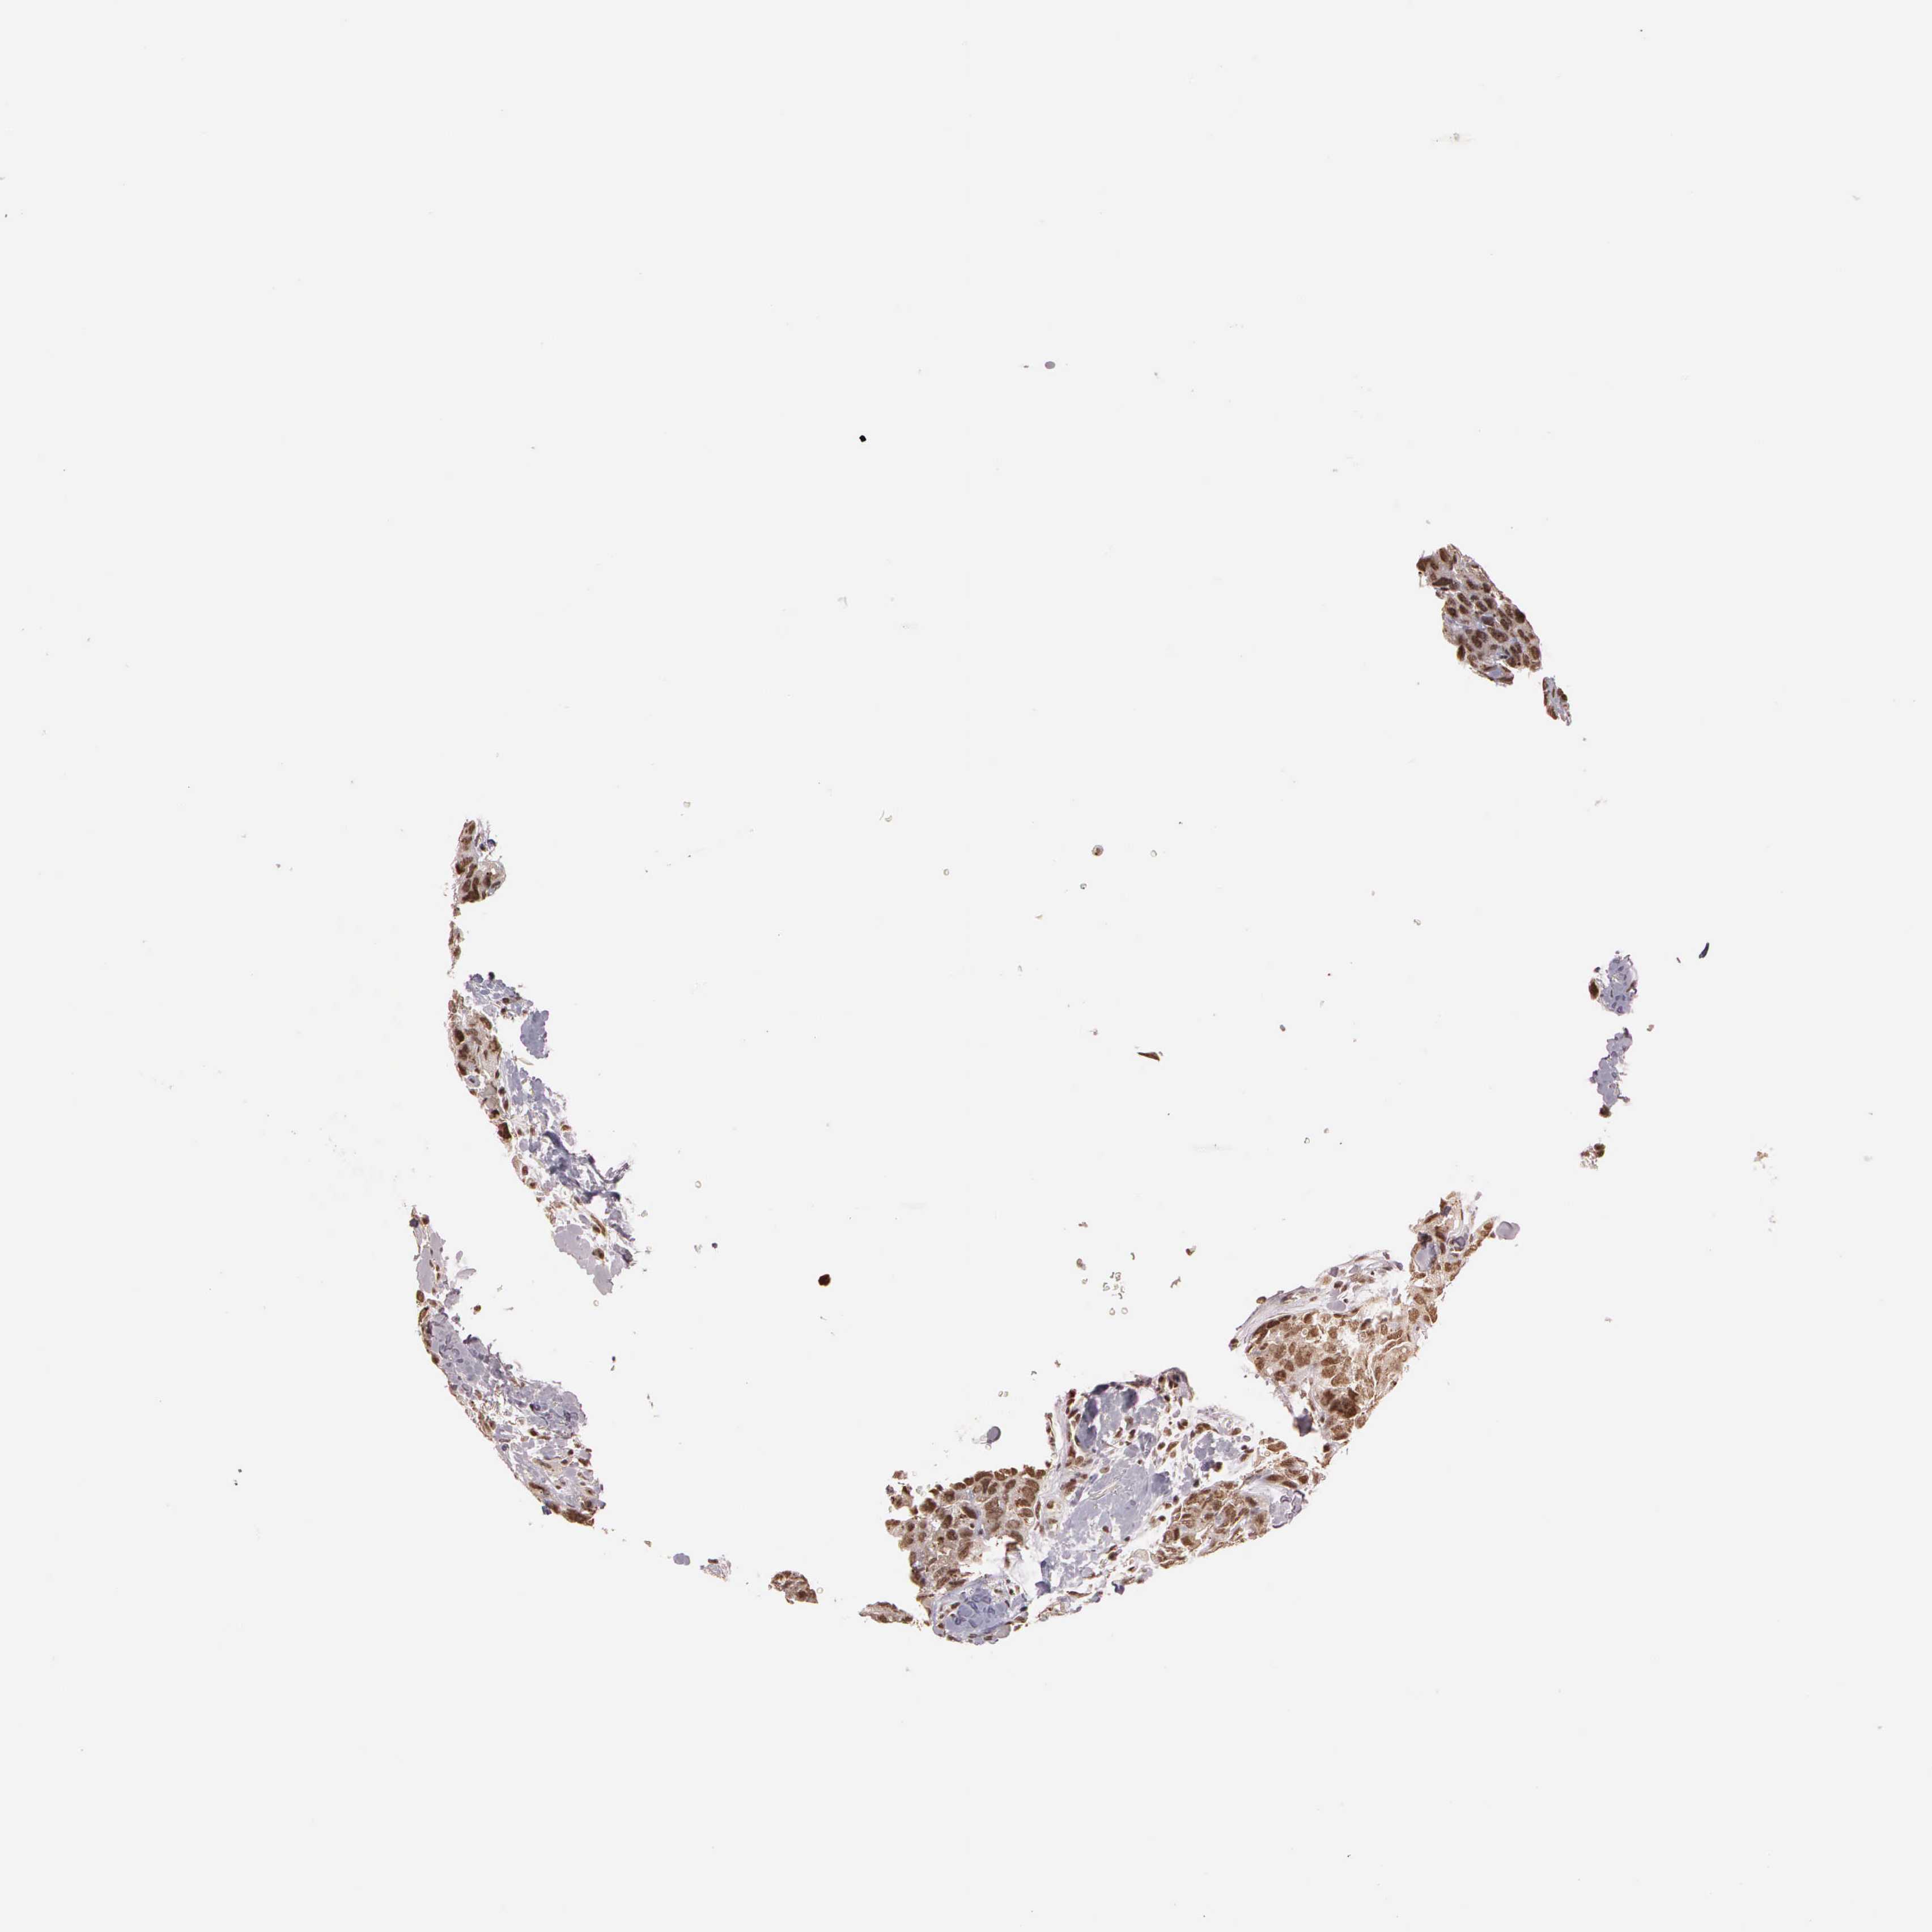

BRCA TCGA BRCA VALIDATION PROTEIN EXPRESSION

ANTIBODIES

AND

VALIDATION